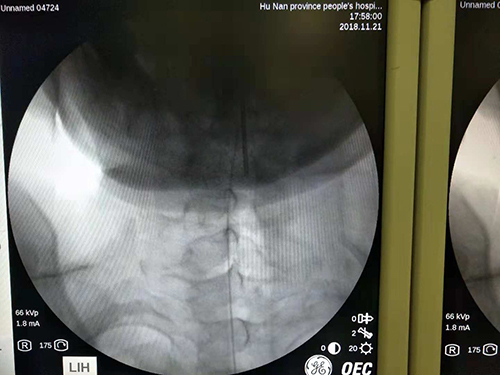

在所有癌痛中,有一种痛叫难治性癌痛,约占癌痛患者中的20%,两个显著的特点是:1、疼痛强度强、爆发痛次数频繁;2、即使镇痛强度最强的吗啡类药物使用到天文数字,仍然无法有效控制疼痛,或者患者无法耐受大剂量镇痛药物的副作用。而难治性癌痛也是当前临床棘手又急需解决的问题。一位27岁的小伙子诊断为结肠癌广泛转移,因颈椎受累与神经压迫,导致左手臂和颈部剧烈疼痛,正常人轻而易举的平躺、转头和抬举手臂,对他来说都是不可能完成的任务,睡一个安稳觉更是一件可望而不可及的事情。在给小伙子实施鞘内镇痛泵植入术,高位颈段置管靶向镇痛这种高难度手术后,小伙子疼痛得到明显缓解,露出了久违的笑容,并可以用那只剧痛难忍的手臂摆出胜利手势的那一刻,应该是医者收到的最好的礼物。“鞘内镇痛泵植入术” 也被誉为癌痛治疗的核武器,该项技术相对全身口服用药有以下几个显著优势:首先脊髓节段靶向镇痛,效果确切;再之,靶向用药大大减少了全身用药量,进而降低了全身毒副反应,理论上口服300mg吗啡可以控制的疼痛,鞘内只需1mg;国内外的新近研究也明确提示,该项技术可以明显提高中晚期癌痛患者的生活质量并延长其生存周期。捷克论坛已成功在肿瘤科、肝胆外科多个病区、老年科、消化内科、呼吸内科、感染科、介入科等多个科室的难治性癌痛患者中实施该项技术。2018年11月实施该项手术9例,均取得临床良好镇痛效果。